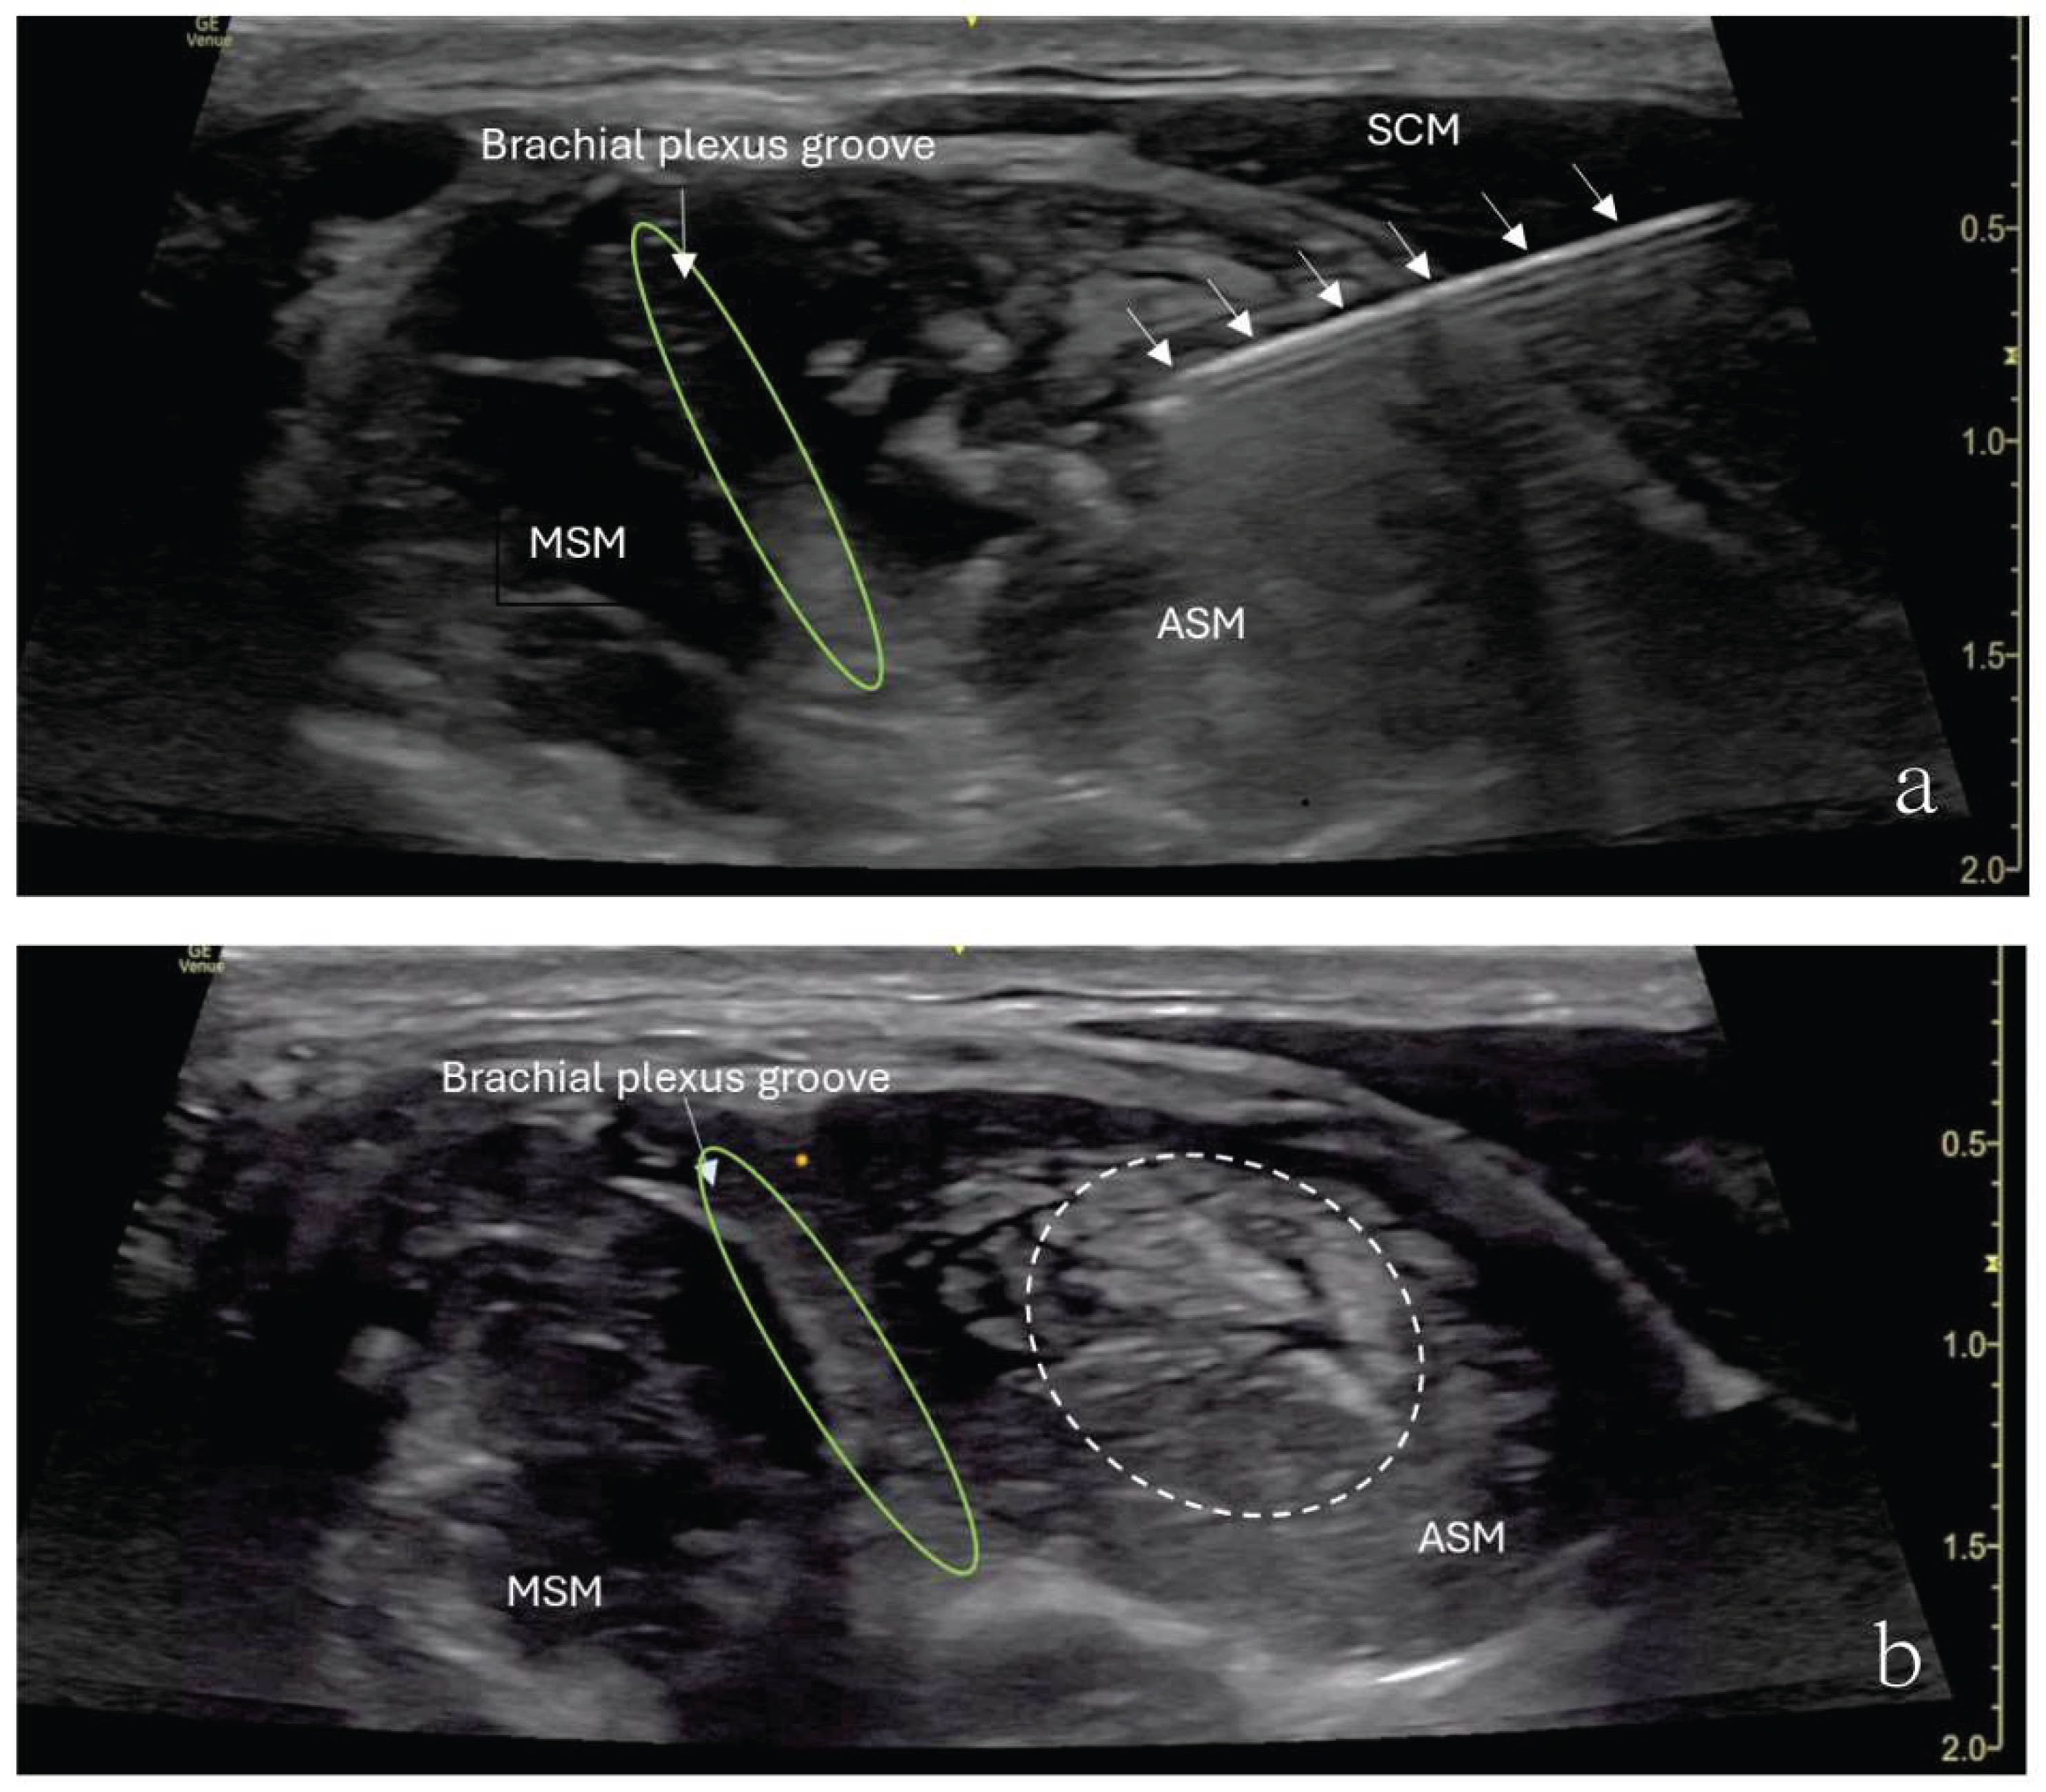

The patient underwent an ultrasound-guided right anterior scalene muscle block under minimal sedation. A high-frequency linear probe was used to identify the anterior scalene muscle (Figure 1). After sterile preparation, A 22-gauge, 50-mm Sono-TAP needle (PAJUNK®, Germany), using an in-plane technique, was advanced from the posterior aspect of the neck anteriorly and was inserted into the middle of the anterior scalene muscle. After negative aspiration for blood, 5 mL of 0.5% ropivacaine was slowly injected in increments. An increased muscle size was noticed with no medication extravasation to the brachial plexus divisions (Figure 1). Sixty minutes after the procedure, the patient’s preexisting numbness disappeared, and her hand strength improved. She experienced no numbness when raising her arm. However, she reported shoulder heaviness and slight weakness, though she had a full range of motion. By 4 hours after the procedure, the weakness in her right shoulder had disappeared. Around 5 hours post-procedure, numbness began returning, starting in the small finger and spreading through the entire arm. Despite this, her hand strength improved, enabling her to write and color.

Figure 1. Ultrasound image showing an anterior scalene muscle block in a 12-year-old girl. (a) SCM sternocleidomastoid muscle, MSM middle scalene muscle, ASM anterior scalene muscle, IJV internal jugular vein. The interscalene nerve roots (C5,6,7) are highlighted with a green circle. (b) The needle (arrows) is inserted into the middle of anterior scalene muscle (ASM) from the posterior aspect of the neck anteriorly, with local anesthetic spreading within the muscle (dashed line). Brachial plexus groove is in between the ASM and MSM.